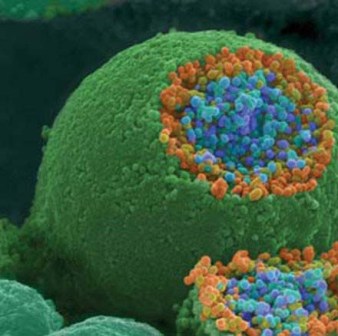

سلول های سرطانی سینه